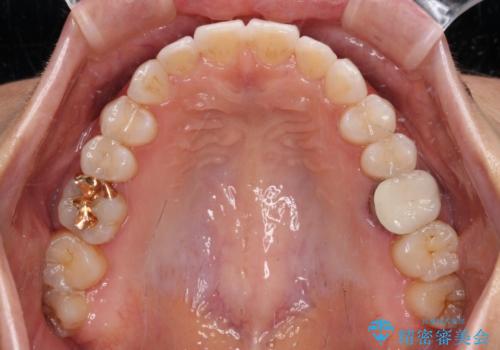

- 前歯のデコボコと上下スペースと前歯の隙間を気にして来院された患者様です。

目立たない装置を希望とのことでインビザラインにより、デコボコを解消しつつ、上下の前歯の隙間を閉じていくこととしました。

デコボコはあっという間に解消されましたが、上下前歯の隙間がなかなか解消されませんでした。

飲み込みの際に舌を前方に突出する癖があり、飲み込みの度に前歯に強く接触していたため、上下前歯の隙間が維持されていました。

舌の訓練を徹底していただいたことで、徐々に隙間は解消され、きれいな歯列に整えることができました。